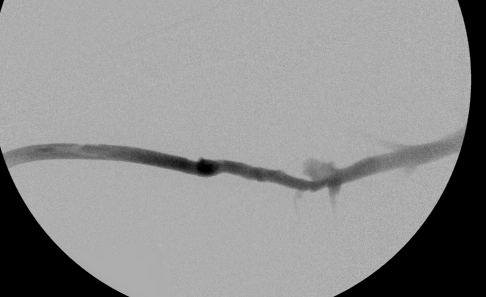

Venous limb stenosis after dilation

Right arm venogram post intervention: complete elimination of the stenosis.